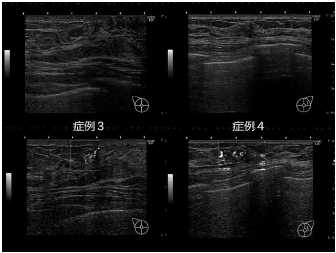

cSoundの画像再構成が可能にした技術として、MVI (Micro Vascular Imaging)がある。こちらは、血流イメージングとして、従来のカラードプラやパワードプラに加え、さらに微細な血流を描出できる技術である。処理能力の向上により、高い分解能とフレームレート(リアルタイム性)および感度の向上を実現させた成果として、小さい腫瘤内に豊富な血流を伴う症例や低エコー域内部の血流を詳細に描出して病変の情報提供に成功した。症例3は楕円形の等エコー腫瘤内部に豊富な血流を描出している(図6 症例3)。乳管内乳頭腫を疑う所見である。症例4は低エコー域の内部の豊富な血流を描出している(図6 症例4)。高度の細胞増殖を伴う乳腺症やDCISを疑う所見である。

右(上段/下段) 症例4 低エコー域の超音波画像(上段 B-mode/下段 MVI)